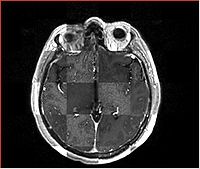

Checkerboard

Builds a "puzzle-piece" collage of blocks from both images, alternating between the two. Helpful if the two images are from different modality or have different contrast. Continuity of edges becomes very apparent on such images.

Case10-FLIRT-axial.jpg